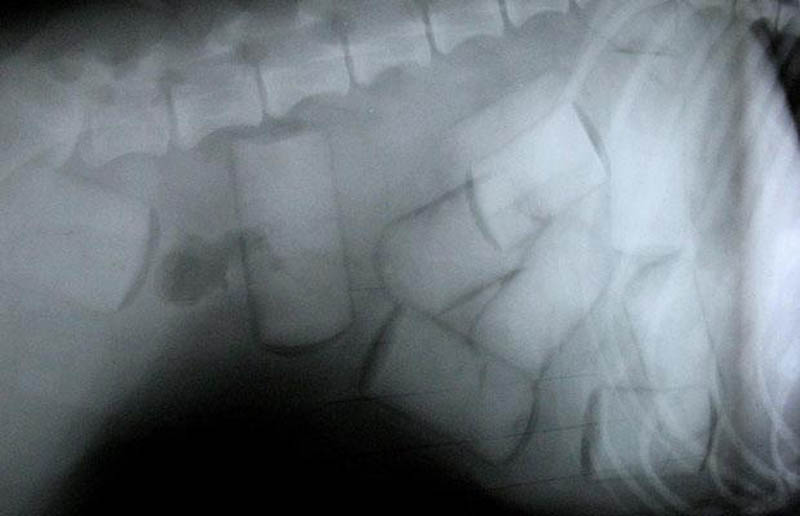

8. Рентгеновский снимок лабрадора, нафаршированного кокаином и готового к путешествию в Европу. (РА)